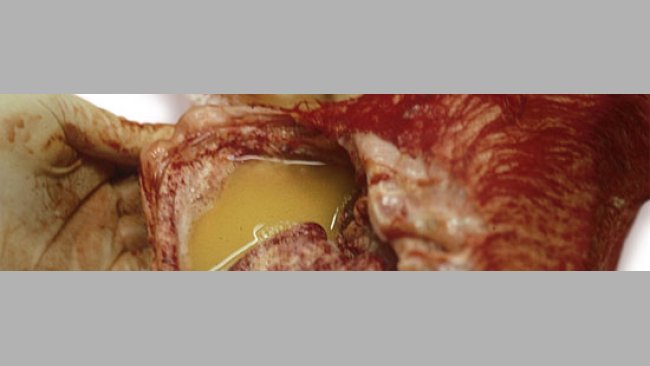

When the clinical signs on the farm and the lesions observed in the piglets lead us to suspect that there is a Haemophilus parasuis infection we have to confirm this diagnosis in the laboratory